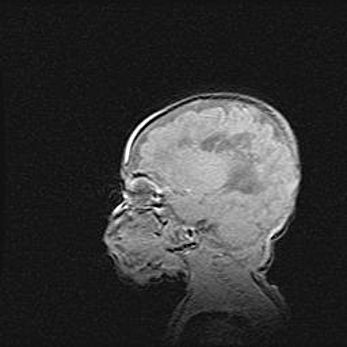

Открытая гидроцефалия.

Возраст: 9 месяцев 12 дней

Вес: 6800 г

Пол: мужской

Окружность головы: 41,5 см

Срок гестации: 28 недель

Гидроцефалия головного мозга у новорожденных имеет характерный признак: опережающий рост окружности головы приводит к визуально хорошо определяемой гидроцефальной форме сильно увеличенного в объёме черепа. Детские неврологи определяют следующие симптомы гидроцефалии у грудничков: выбухающий напряжённый родничок, частое запрокидывание головы, смещение глазных яблок к низу.